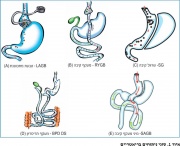

| 19:18, 2 במרץ 2016 | Bariatric4.png (קובץ) |  |

45 קילו־בייטים | Motyk | 1 | |

| 22:48, 21 בפברואר 2016 | בריאטרי1.jpg (קובץ) |  |

146 קילו־בייטים | Motyk | 1 | |

| 16:29, 21 בפברואר 2016 | CoverBeriatry.png (קובץ) |  |

246 קילו־בייטים | Motyk | 2 | |